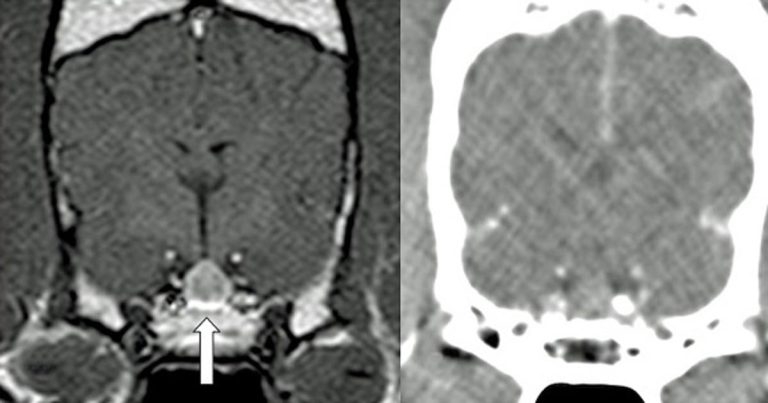

It is important to recognise complete removal of the pituitary gland is usually performed (Figure 1); therefore, these patients require lifelong supplementation of thyroxine and cortisone. All patients require immediate postoperative desmopressin administration, but, in most cases, this can be weaned in the first few months following surgery. Of course, complications are possible, which include incomplete tumour removal, haemorrhage, infection and recurrence. As such, owners need to be fully informed prior to choosing this treatment modality for their pet.